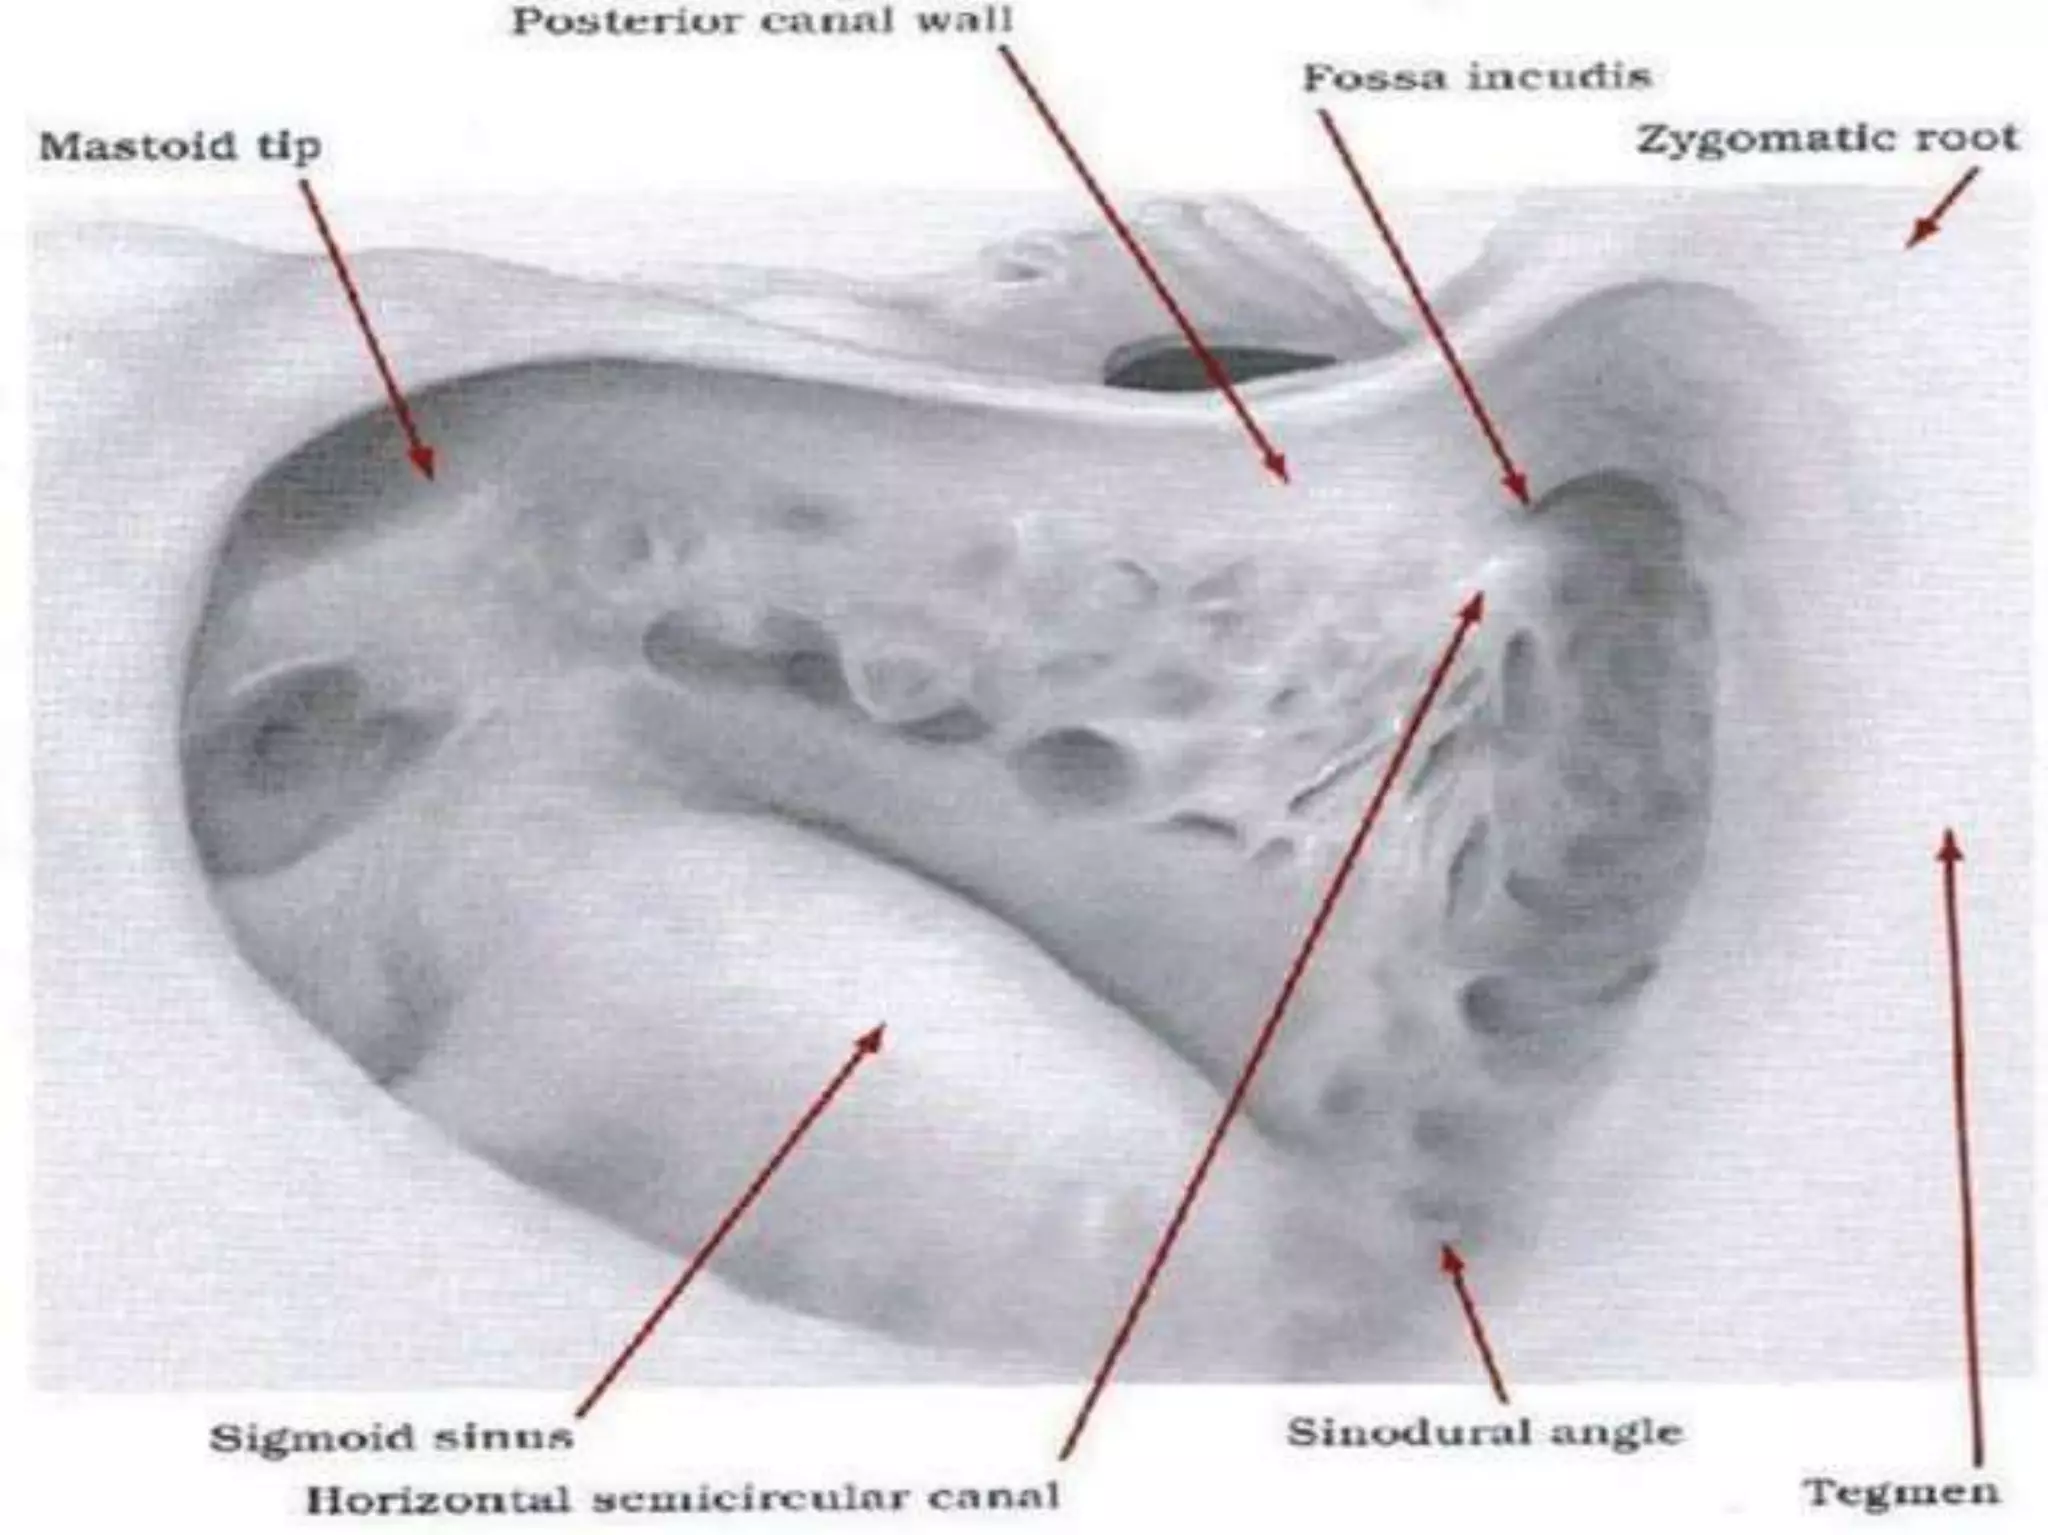

Chronic otitis media is a chronic inflammation of the middle ear and mastoid cavity that presents with recurrent ear discharge through a perforated eardrum. It has several subtypes depending on the state of the eardrum perforation and epithelium. It can be caused by prior acute otitis media, genetics, environment, eustachian tube issues, gastroesophageal reflux disease, craniofacial abnormalities, or immune deficiency.